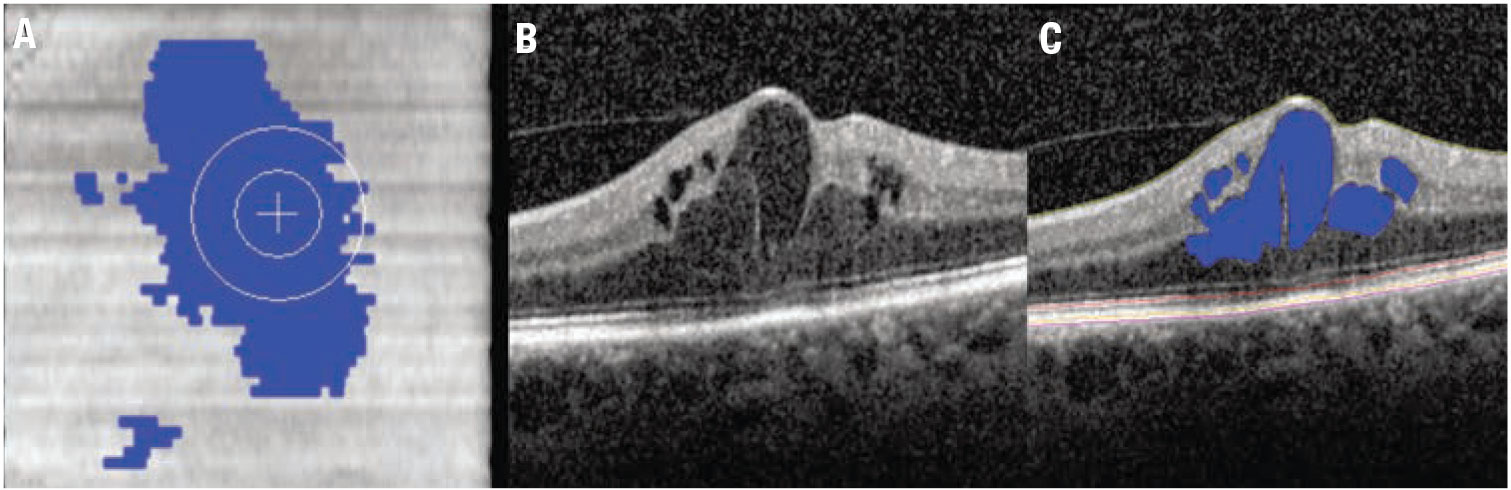

Figure 1. Automated fluid feature detection and optical coherence tomography biomarker detection in diabetic macular edema. A) Fundus OCT image demonstrates en face fluid distribution map. B) Foveal B-scan with significant foveal fluid. C) Foveal B-scan with intraretinal fluid automated segmentation (blue) and multi-layer segmentation lines. |

Multi-layer segmentation platforms, including machine learning-enhanced systems, are now able to provide quantitative outputs for zones and inter-layer thickness/volumes that can be linked to function and other structural dynamics.1-3 Quantitative fluid object characterization now provides next-generation detail of fluid burden and impact on overall disease outcomes and therapeutic response.

The RFI represents the percentage of overall retinal volume from the internal limiting membrane to the retinal pigment epithelium that is composed of retinal fluid (measured as a percentage).6 This biomarker has been demonstrated to be associated with functional outcomes and early instability in RFI during the treatment phase has been linked to long-term volatility to treatment response (Figure 1).6,8